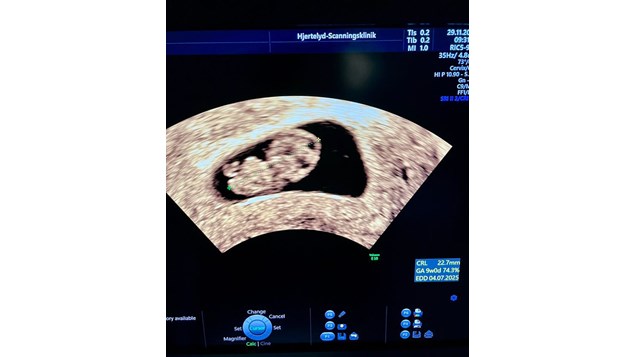

22 mm 'stor' nu. For 2 uger siden var målet bare 8 mm.

Hjertets frekvens er lige nu 167 slag/min - om bare 3 døgn er det færdigdannet

Livets lille store mirakel